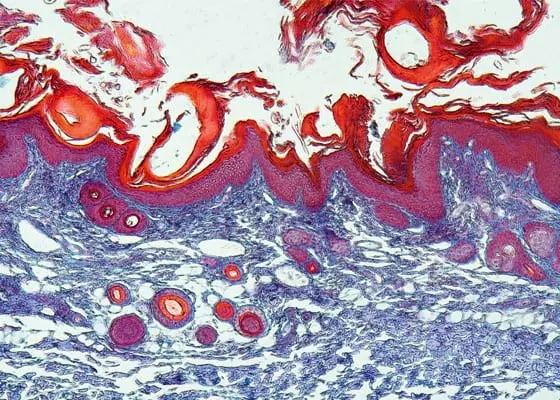

Świerzb – postępowanie i leczenie u dzieci

• prof. dr hab. n. med. Joanna Narbutt , lek. Michał Niedźwiedź